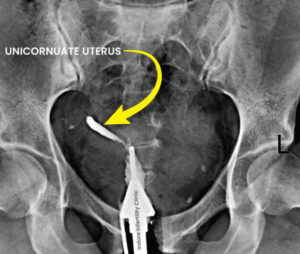

Unicornuate Uterus